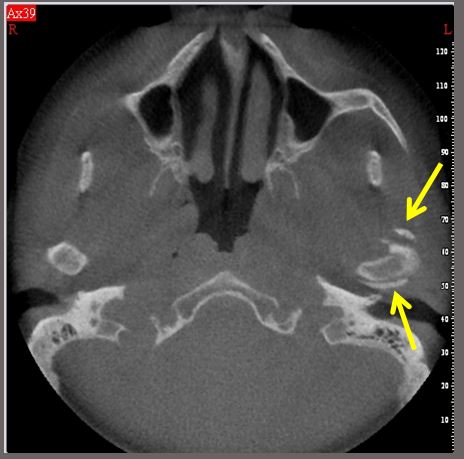

Synovial chondromatosis .

- It is a rare benign disorder characterized by metaplastic formation of multiple osseocartilaginous nodules within the synovial membrane of the joints.

- Imaging features: multiple radiopaque loose bodies within the synovial fluid and joint space surrounding the condylar head. In advanced stages of the disease sclerosis and erosion of condylar head and glenoid fossa may be seen.